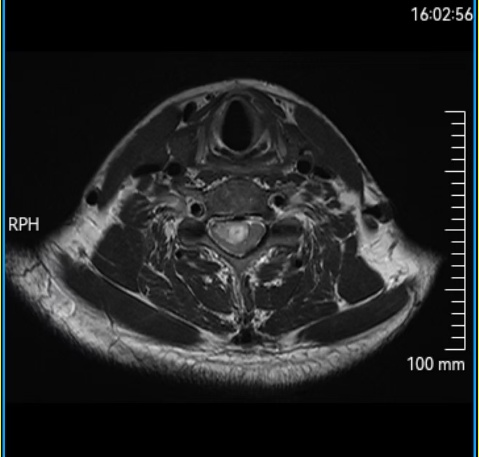

三个月前,55岁的王先生开始出现颈部僵硬、左腿无力、行走不稳等症状。经西安市红会医院颈椎病区系统检查,发现其颈椎椎管内有一个长约4厘米的肿瘤,严重压迫脊髓,导致神经功能进行性受损。

“肿瘤位于颈髓腹侧,与脊髓粘连紧密,手术操作空间狭小,稍有不慎即可能导致患者永久性瘫痪。”医生表示,颈椎管内本已空间有限,肿瘤进一步挤压脊髓,使其仅存薄薄一层,手术难度与风险极高。

手术当天,在3D显微镜的高清视野下,主刀医生开始了在“生命禁区”的精细操作。肿瘤与正常脊髓组织边界模糊,周围血管密布,每一步都需精准而谨慎。

“如同在豆腐上雕刻,既要彻底切除肿瘤,又必须保护脊髓不受损伤。”张永远医生这样形容。手术团队借助先进的3D显微镜与显微器械,细致分离肿瘤与脊髓组织,完整保留脊髓结构。历经近5小时的精细手术,肿瘤被彻底切除。术后第二天,王大爷左腿肌力明显恢复,行走稳定性显著改善,手术取得预期效果。